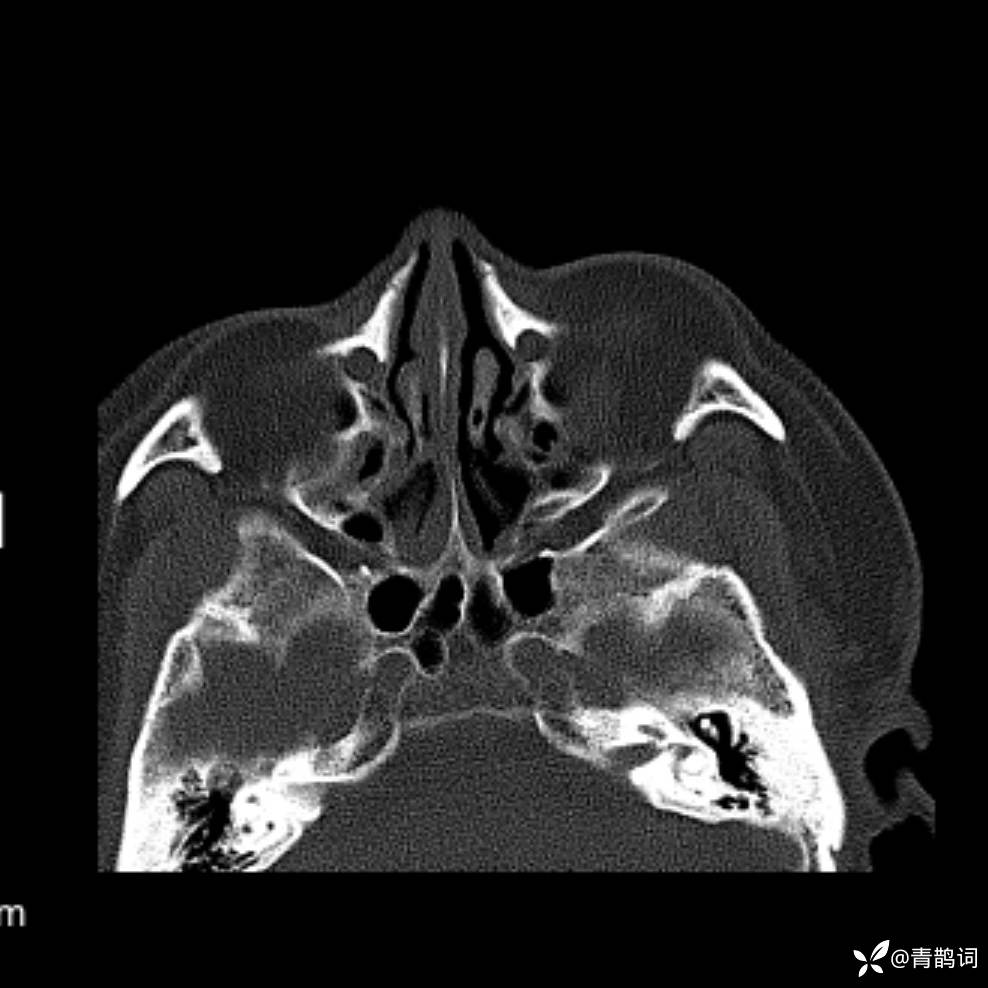

患者年龄:30岁。

患者性别:男。

简要病史:左颜面部肿胀2年,反复咳嗽咳痰,逐渐加重。

结合病史及影像学表现,期待评论区各位老师各抒己见~

木村病 (14)